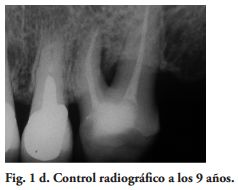

Al momento del examen, 10 (90.9%) EC estaban en función en 10 pacientes. Un molar 26, restaurado con EC, se perdió por enfermedad periodontal después de 12 años y 9 meses en función. Ninguna restauración se desprendió, no hubo recidiva de caries y al examen radiográfico no se observaron lesiones patológicas en los 10 DPET en función (Figs. 1a,1d; 2c; 3c,3d; 4c).

Los exámenes clínicos fueron realizados con un espejo y un explorador agudo. Un control radiográfico fue hecho en cada DPET. La evaluación de las variables relacionada a las restauraciones, fue ciega entre los autores. El Coeficiente Kappa de Cohen (14), en la calidad de las restauraciones y del examen radiográfico, varió de 0.78 a 1 [excelente de acuerdo a la guía de Fleiss (15). En los casos de no concordancia en la calificación, se registró el valor más bajo.